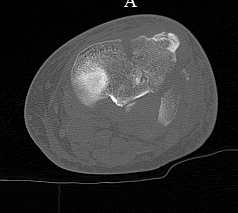

[Ortho] перелом проксимальной тибии + вывих бедра

Серия КТ сканов в аппарате